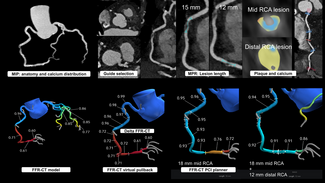

The patient was sent for coronary artery catheterization that was performed via right radial artery approach (6 Fr Glidesheat and 5 Fr Optitorque radial TIG catheter Terumo interventional systems). The angiographic findings were a mild mid left main coronary artery (LMCA) lesion, a partially recanalized chronic left anterior descending (LAD) coronary artery proximal occlusion with excellent collaterals, severe proximal left circumflex (LCX), mid obtuse marginal (OM) stenosis (Figure 1A), and a severe stenosis of the bifurcation compromising the posterior descending and posterolateral branches of the right coronary artery (not shown in figures).

The patient was sent for coronary artery catheterization that was performed via right radial artery approach (6 Fr Glidesheat and 5 Fr Optitorque radial TIG catheter Terumo interventional systems). The angiographic findings were a mild mid left main coronary artery (LMCA) lesion, a partially recanalized chronic left anterior descending (LAD) coronary artery proximal occlusion with excellent collaterals, severe proximal left circumflex (LCX), mid obtuse marginal (OM) stenosis (Figure 1A), and a severe stenosis of the bifurcation compromising the posterior descending and posterolateral branches of the right coronary artery (not shown in figures).

The patient refused coronary artery bypass graft surgery and we therefore performed a percutaneous coronary intervention (PCI) by the radial artery approach. The LMCA was engaged with an EBU 3.5 6 Fr guiding catheter. The LAD occlusion was crossed using a 0.014” Pilot 50 guidewire (Abbott Vascular), and subsequently pre-dilated with a 2.0 mm x 20 mm Maverick (Boston Scientific) in several occasions at 10 atm of pressure, achieving TIMI 2 coronary artery flow. We then deployed 2 overlapping Endeavor Resolute cobalt-chromium drug-eluting stents (DES) (Medtronic Inc.) at 12 atm from distal to proximal, 2.5 mm x 30 mm and 2.75 mm x 24 mm, respectively. During the delivery of the proximal stent, a type B dissection developed within the ostium of the LAD extension and anterograde flow compromise (Figure 1B), which forced us to deploy another ostial 2.75 mm x 18 mm overlapped Endeavor Resolute DES despite the risk of jailing the origin of the LCX. The stent was deployed at 12 atm with good angiographic result re-establishing TIMI 3 flow.

A 0.014” BMW guidewire (Abbott Vascular) was then used to cross into the LCX to perform PCI to the OM immediately distal to a posterolateral branch. While trying to cross with a stent (2.5 mm x 15 mm Promus platinum-chromium DES [Boston Scientific]) through the LMCA into the LCX, the stent was detached from the delivery balloon, subsequently jamming the ostial LAD stent (Figure 1C). This precluded the possibility to further advance the stent to the distal segment of the OM and prevented deployment at the actual detached position due to the compromise of the LMCA, LAD ostial stent, and LCX, which were not the intended segments to treat. Fortunately we were able to maintain wire position across the non-expanded stent. A new 1.5 mm x 12 mm Sprinter coronary balloon (Medtronic) was positioned distal to the detached stent (Figure 2A), and applying low atmospheres for its inflation, we pulled the system (balloon-stent-guidewire-guiding catheter) back into the distal radial artery and removed it, including the glide sheath, without damaging the radial artery.

A 0.014” BMW guidewire (Abbott Vascular) was then used to cross into the LCX to perform PCI to the OM immediately distal to a posterolateral branch. While trying to cross with a stent (2.5 mm x 15 mm Promus platinum-chromium DES [Boston Scientific]) through the LMCA into the LCX, the stent was detached from the delivery balloon, subsequently jamming the ostial LAD stent (Figure 1C). This precluded the possibility to further advance the stent to the distal segment of the OM and prevented deployment at the actual detached position due to the compromise of the LMCA, LAD ostial stent, and LCX, which were not the intended segments to treat. Fortunately we were able to maintain wire position across the non-expanded stent. A new 1.5 mm x 12 mm Sprinter coronary balloon (Medtronic) was positioned distal to the detached stent (Figure 2A), and applying low atmospheres for its inflation, we pulled the system (balloon-stent-guidewire-guiding catheter) back into the distal radial artery and removed it, including the glide sheath, without damaging the radial artery.

We decided to gain right femoral artery access in order to use a 7 Fr system to improve guiding catheter support, alignment, and to protect the LAD during performance of a certainly difficult procedure. The first angiogram showed the presence of a longitudinal compression of the ostial LAD stent (Figure 2B) probably due to the previous forceful withdrawal of the detached and jammed stent with secondary and involuntary deep guiding catheter intubation. We decided to wire the LCX and the LAD with BMW guidewires and, taking advantage of the longitudinal compression of the LAD stent, we were able to easily advance balloons and stents into the distal segments of the OM (Figure 3A). Then 2 non-overlapped Endeavor Resolute DES (2.5 mm x 18 mm an 2.75 mm x 24 mm) were delivered to the LCX without difficulties, resulting in a good final angiographic result with no further compromise of the ostial LAD stent.

We decided to gain right femoral artery access in order to use a 7 Fr system to improve guiding catheter support, alignment, and to protect the LAD during performance of a certainly difficult procedure. The first angiogram showed the presence of a longitudinal compression of the ostial LAD stent (Figure 2B) probably due to the previous forceful withdrawal of the detached and jammed stent with secondary and involuntary deep guiding catheter intubation. We decided to wire the LCX and the LAD with BMW guidewires and, taking advantage of the longitudinal compression of the LAD stent, we were able to easily advance balloons and stents into the distal segments of the OM (Figure 3A). Then 2 non-overlapped Endeavor Resolute DES (2.5 mm x 18 mm an 2.75 mm x 24 mm) were delivered to the LCX without difficulties, resulting in a good final angiographic result with no further compromise of the ostial LAD stent.

Finally balloon re-expansion of the DES longitudinal compression was performed with a Voyager (Abbott Vascular) 3.0 mm x 12 mm at 12 atm (Figure 3B), with complete resolution of the stent compression and a good final angiographic result (figure 3C).